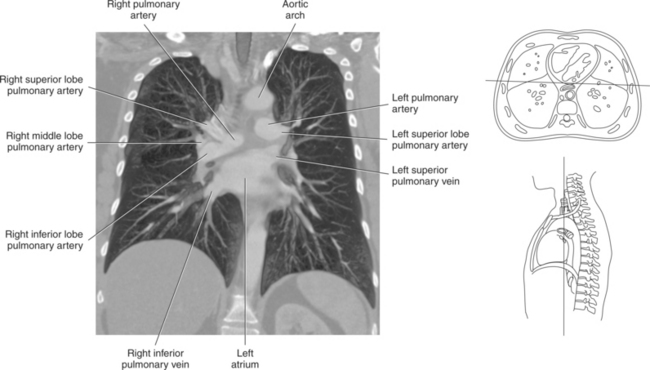

Blood travels to and from the heart through the great vessels, which include the aorta, pulmonary arteries and veins, and superior and inferior venae cavae (Figures 6.54 and 6.55). The aorta is the largest artery of the body and can be divided into the ascending aorta, aortic arch, and descending aorta. The ascending aorta begins at the base of the left ventricle at the level of the sternal angle, then curves superiorly and posteriorly as the aortic arch over the root of the left lung. The top of the aortic arch is approximately at T3 (Figures 6.56 and 6.57). The arch continues as the descending aorta posterior to the left bronchus and pulmonary trunk, on the left side of the vertebral body of T4 (Figures 6.58 and 6.59). The descending aorta passes slightly anterior and to the left of the vertebral column as it descends through the thoracic and abdominal cavities (Figure 6.60). While in the thoracic cavity, the descending aorta is commonly called the thoracic aorta, and while in the abdominal cavity, it is called the abdominal aorta. The pulmonary trunk is the origin of the right and left pulmonary arteries and lies entirely within the pericardial sac. It arises from the right ventricle and ascends in front of the ascending aorta, courses posteriorly and to the left, where it bifurcates at the level of the sternal angle (T4) into the right and left pulmonary arteries (Figures 6.61 through 6.63). The pulmonary trunk is attached to the aortic arch by a fibrous cord called the ligamentum arteriosum, the remnant of an important fetal blood vessel (ductus arteriosus) that links the pulmonary and systemic circuits during fetal development (Figures 6.54 and 6.61). The right pulmonary artery courses laterally, posterior to the ascending aorta and superior vena cava, and anterior to the esophagus and right mainstem bronchus, to the hilum of the right lung. At the root of the right lung, the right pulmonary artery divides into two branches, with the lower branch supplying the middle and inferior lobes and the upper branch supplying the superior lobe (Figures 6.61 through 6.64). The left pulmonary artery, shorter and smaller than the right, is also the most superior of the pulmonary vessels. It travels horizontally, arching over the left mainstem bronchus, and enters the hilum of the left lung just superior to the left mainstem bronchus (Figures 6.61 through 6.64). Within the lungs, each pulmonary artery descends posterolateral to the main bronchus and divides into lobar and segmental arteries, continuing to branch out and to follow along with the smallest divisions of the bronchial tree (Figures 6.61 and 6.64). Located inferior to the pulmonary arteries are the four pulmonary veins, two each (superior and inferior) extending from each lung to enter the left atrium (Figures 6.54, 6.55, 6.61, and 6.64 through 6.68). They commence in a capillary network along the walls of the alveoli, where they are continuous with the capillaries of the pulmonary arteries. The venous capillaries merge to form small vessels that unite successively to eventually form a single trunk for each lobe: three for the right and two for the left lung. Frequently the trunk from the middle lobe of the right lung unites with the trunk from the upper lobe, forming just two trunks on the right side prior to entering the left atrium. The right superior pulmonary vein collects blood from the upper lobe segments of the right lung and passes anterior and inferior to the right pulmonary artery, behind the superior vena cava. The right inferior pulmonary vein receives blood from the right lower lobes of the lung and crosses behind the right atrium to the left atrium (Figures 6.61 and 6.69 through 6.71). The left superior pulmonary vein receives blood from the left upper lobe of the left lung and courses anterior and inferior to the left main bronchus as it enters the left atrium. The left inferior pulmonary vein drains the inferior lobe of the left lung and passes toward the left atrium anterior to the bronchi (Figures 6.61 and 6.72 through 6.74). The pulmonary veins course more horizontally than the pulmonary arteries and are ultimately oriented toward the left atrium. At the root of the lungs, the pulmonary veins are anterior to the pulmonary arteries, which are anterior to the bronchus. While within the lungs, the branches of the pulmonary arteries are anterior to the bronchi, which are anterior to the pulmonary veins. The superior and inferior venae cavae are the largest veins of the body. The superior vena cava is formed by the junction of the brachiocephalic veins, posterior to the right first costal cartilage, and carries blood from the thorax, upper limbs, head, and neck (Figure 6.24). As it travels inferiorly, it is located posterior and lateral to the ascending aorta before entering the upper portion of the right atrium (Figures 6.54 through 6.59). The inferior vena cava is formed by the junction of the common iliac veins in the pelvis and ascends the abdomen to the right of the abdominal aorta and anterior to the vertebral column. It passes through the caval hiatus of the diaphragm and almost immediately enters the inferior portion of the right atrium (Figures 6.75 and 6.76).